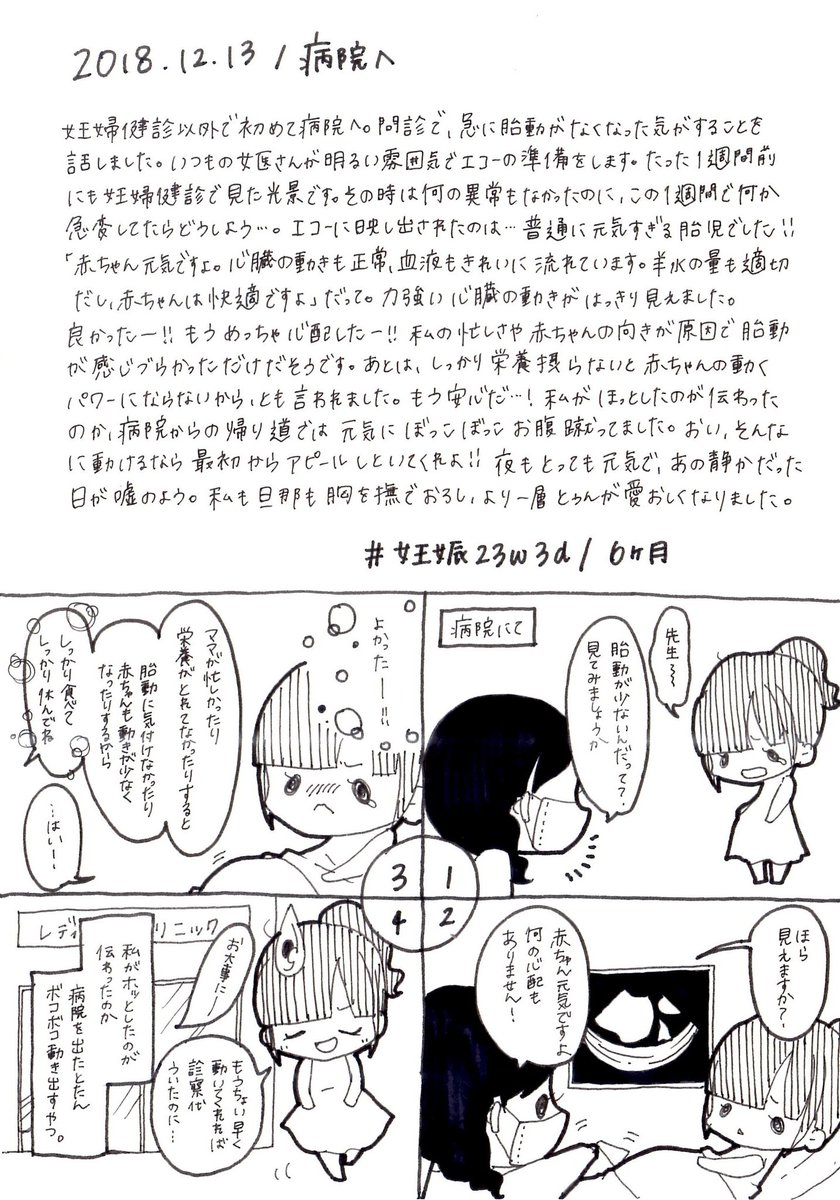

2018.12.11 いつも痛いくらいの胎動、丸1日感じなかった日がありました。 見逃しただけ?いや、やっぱり何かおかしい…ということで、病院へ行くことに。 赤ちゃん、どうか無事でいて! #育児漫画 #育児日記 #妊娠 #妊娠中期 #胎動 #妊娠6ヶ月 #イラスト好きさんと繋がりたい #ママ垢さんと繋がりたい pic.twitter.com/zO0oJrfS9b

2018.12.12 丸1日以上経っても胎動が感じられないように思い、不安でいてもたってもいられず意を決して病院へ。 ママと赤ちゃんは文字通り一心同体だからね。不安が赤ちゃんにも伝わっちゃってたのかも。 #育児漫画 #育児日記 #妊娠 #妊娠中期 #胎動 #エコー #妊娠6ヶ月 #ママ垢さんと繋がりたい pic.twitter.com/uvQfJcuudI